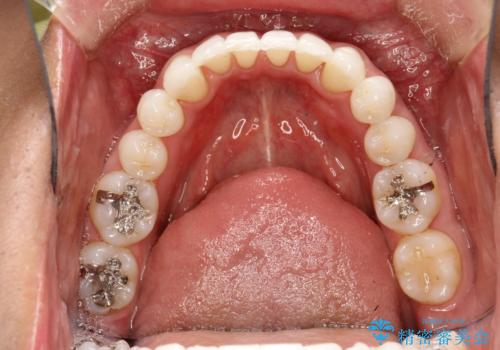

インビザライン終了時のPMTC

- インビザライン治療が終了し、アタッチメント除去の際にクリーニング(PMTC)も希望されました。

PMTC60分1万円+tax(保険適応外)を行いました。

インビザライン矯正治療は、歯にアタッチメント(歯を動かすための突起物)をつけます。そのため、矯正治療が終了し、アタッチメントを外すと着色が目立つことがあります。矯正治療の終了のタイミングではクリーニングを行い、着色の除去や歯と歯の間・歯と歯肉との境目などのケアをしっかりすることをおすすめしています。